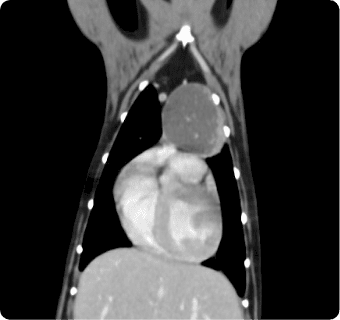

빠른 촬영속도를 통해 마취시간을 최소화 하며, 선명한 3차원 영상을 구현합니다.

종양, 전이평가, 선천적 혈관 기형 등 여러 질환의 조기 발견 및 환자상태를 평가합니다.

폐 실질 평가, 폐 염전, 폐 종양, 종격동 종양, 심장종양, 폐 전이 평가, 기관, 기관지, 식도의 평가, 복막심낭횡격막탈장, 동맥관개존증

간, 비장, 소화기, 콩팥, 방광, 부신의 종양, 간문맥전신단락, 복강 내 실질 장기 평가, 요로결석에 의한 폐색 평가